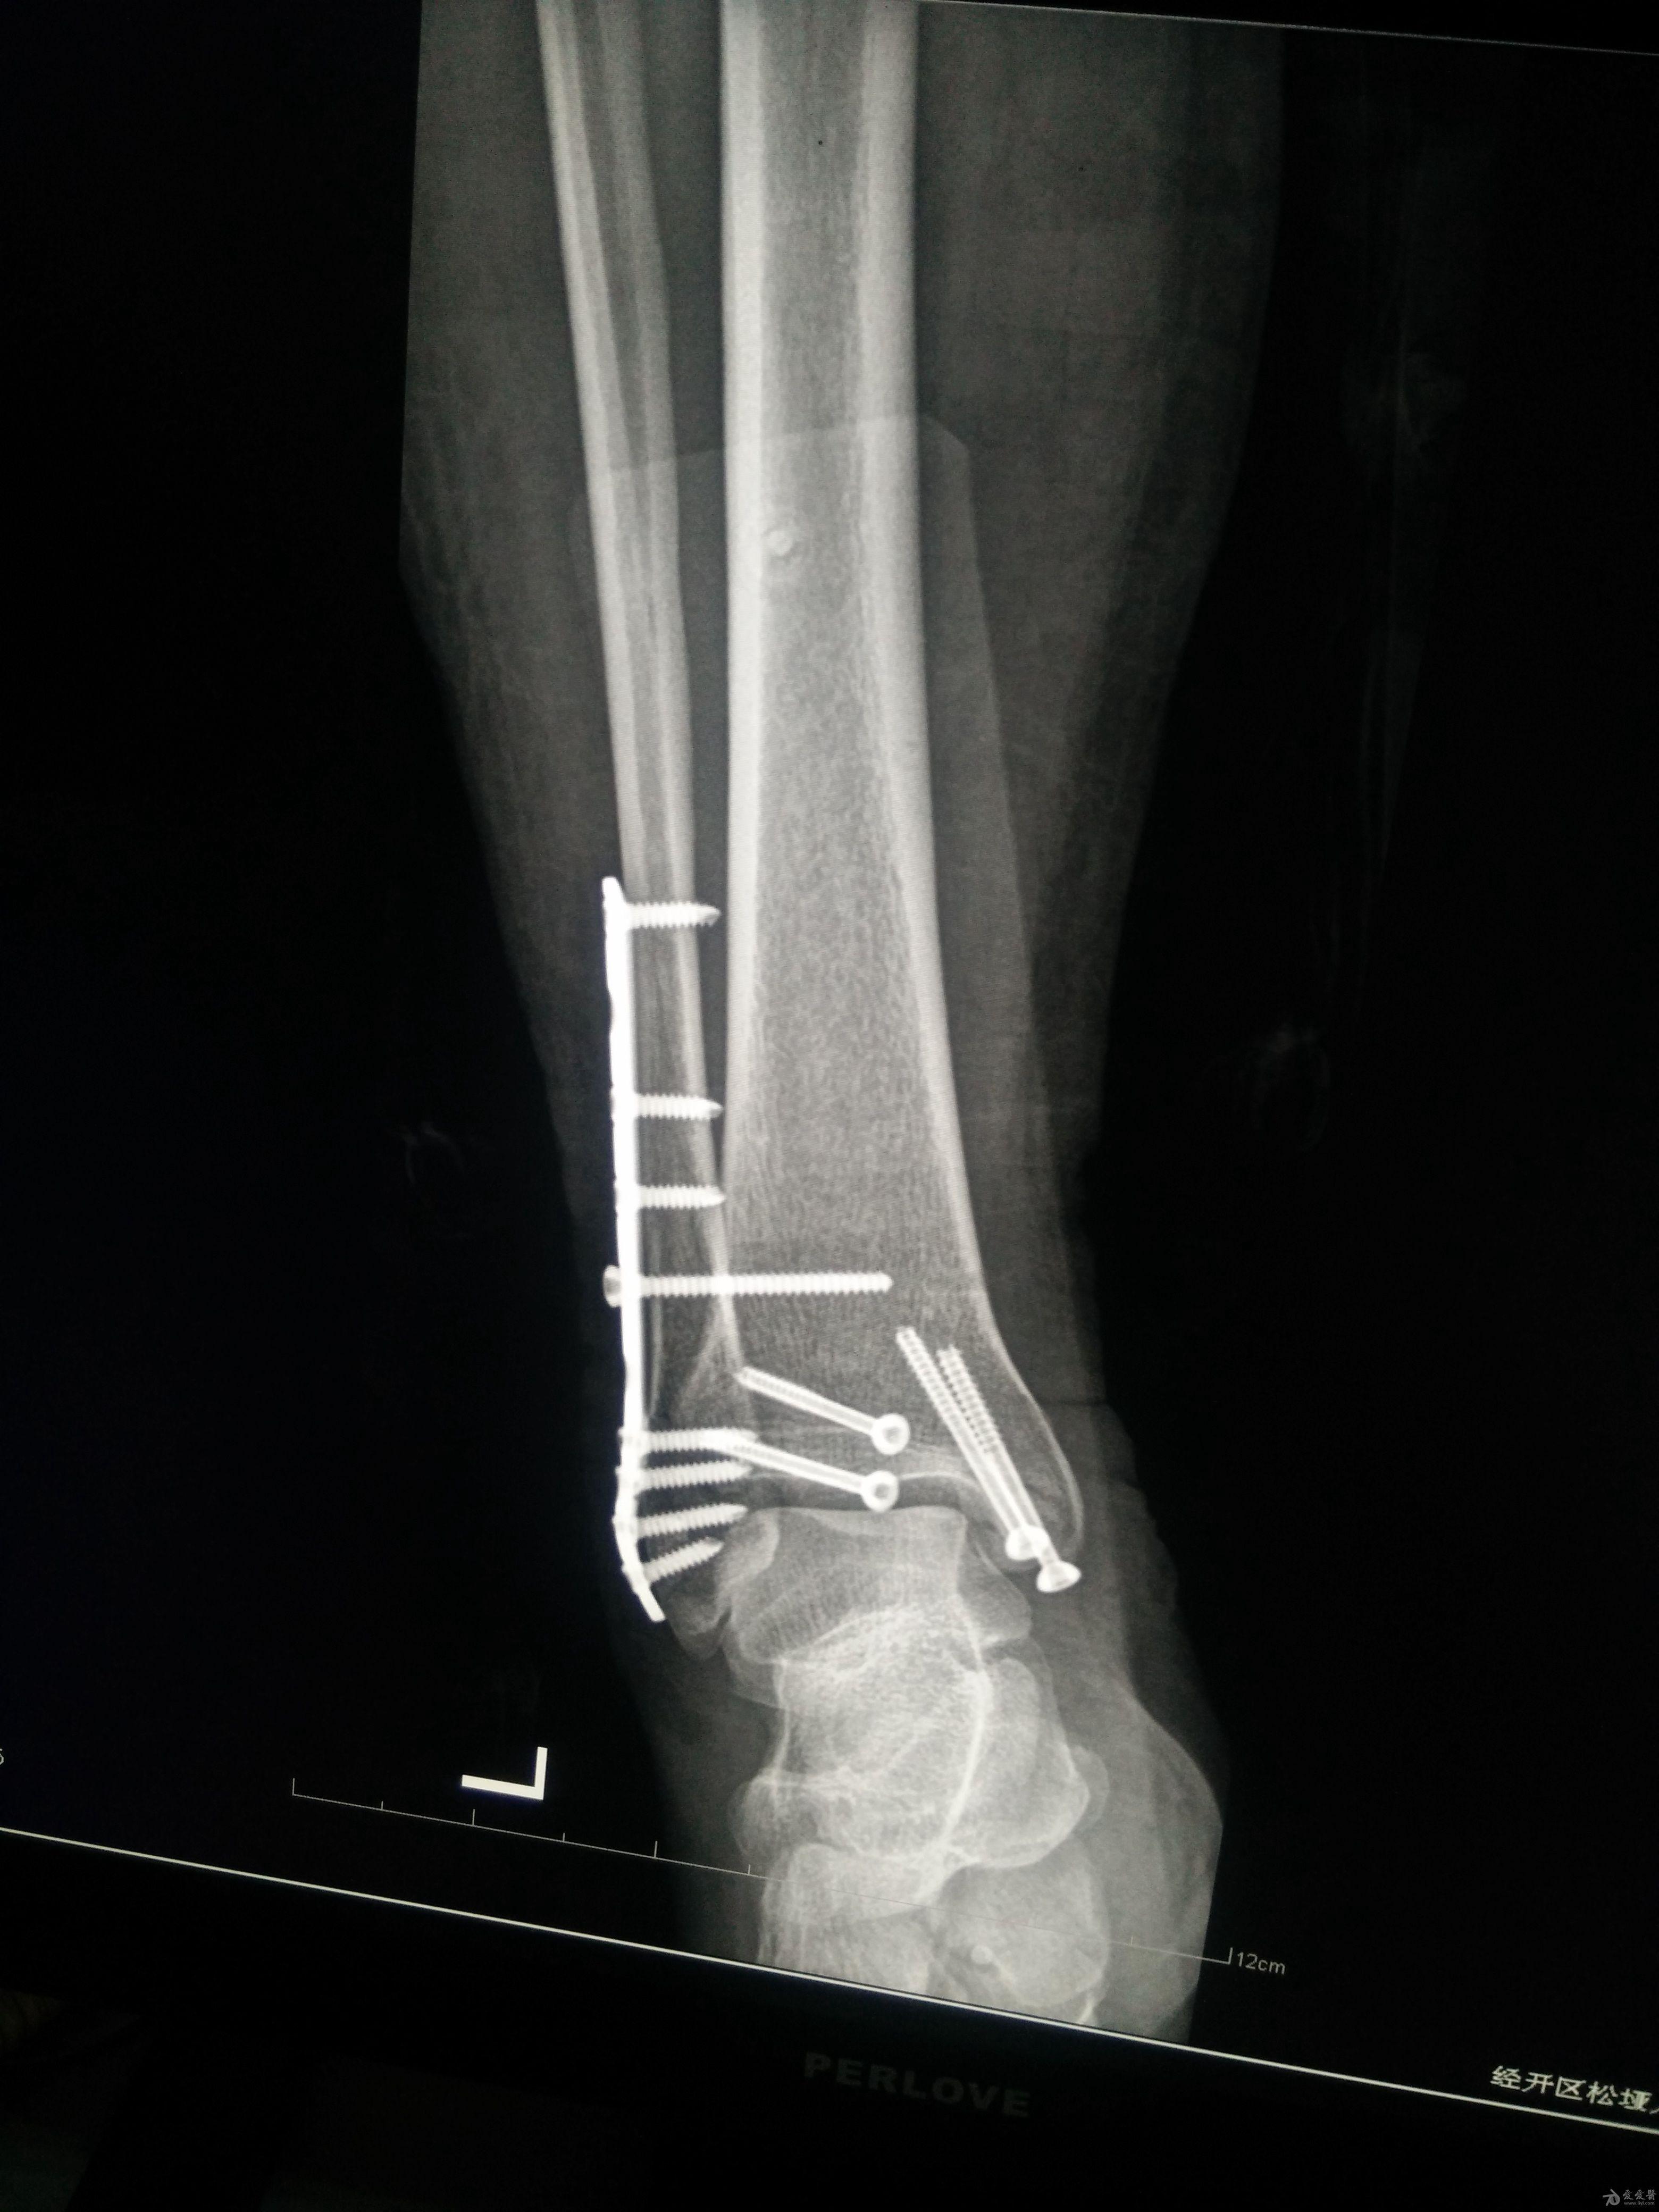

左三踝骨折手术治疗

患者女,外伤后左踝关节活动受限1小时入院,

入院后查体:左踝关节肿胀,活动受限,行DR及左踝关节CT检查,如下图,手术待肿胀消退后行手术治疗,目前愈合良好,请问问各位老师,好久可以下地呀, 下胫腓联合镙钉3个月取呀,

这个下胫腓螺钉真的没有必要打,另外后踝的两枚螺钉怪怪的,从后往前打的,看着钉子帽偏内侧,这个应该在外侧才对,

下胫腓联合单钉固定小心断钉

下胫腓拉力钉一般一个月到一个半月取出!下地需骨折愈合情况而定,下地时需拄拐,患肢尽量不负重行走。